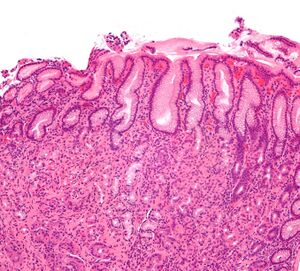

صورة مجهرية لالتهاب المعدة . صبغة الهيماتوكسيلين والإيوسين. | |